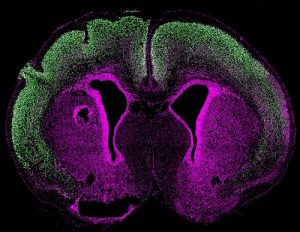

Mehr erfahren zu: "Wie schädigt zuviel Interferon das Gehirn von ungeborenen Kindern?" Wie schädigt zuviel Interferon das Gehirn von ungeborenen Kindern? Forscher der Universitätsmedizin Göttingen (UMG) erstellen das erste Tiermodell, mit dem schädigende Mechanismen von übermäßiger Interferonausschüttung auf das Gehirn untersucht werden können.